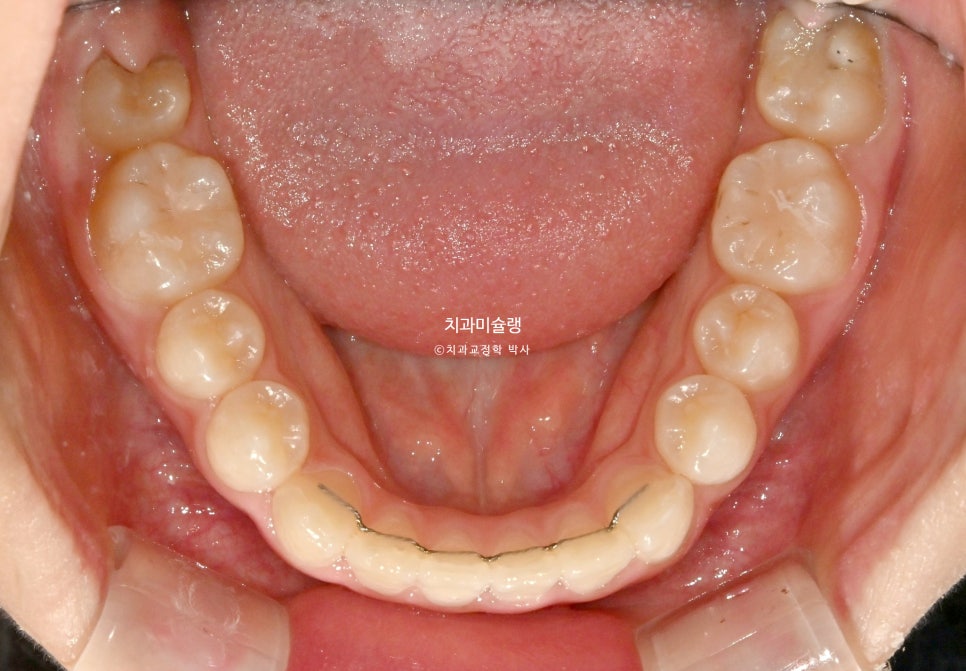

치료 완료 시 결과

중심선은 잘 맞으며 절단교합으로 인항 개방교합은 해소되었습니다.

어금니 교합관계는 1급을 달성.

3급 교합관계를 1급으로 만들기 위해 치료기간 내내 3급 고무줄을 사용했습니다.

결과가 성인교정치료 결과에 준한만큼 유지장치도 성인과 동일하게 들어갑니다.